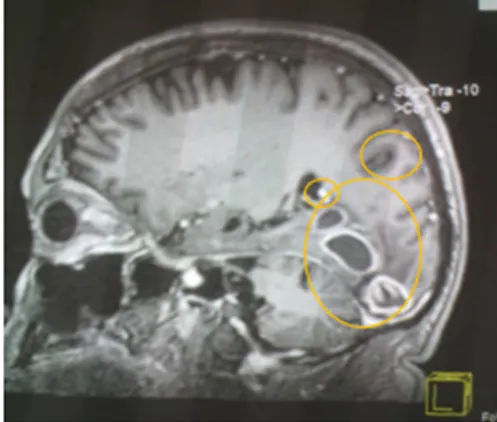

• En vista de compromiso Neurológico se solicita Resonancia Magnética Cerebral donde se evidencia:

Conclusiones del estudio Rx

En el presente estudio se observan múltiples imágenes quísticas de neurocisticercosis, de diferentes tamaños y en diferentes fases, vesicular, nodular y calcificadas, siendo la de gran tamaño la de localización parieto occipital derecha, con importante edema perilesional que genera efecto de masa desplazando estructuras y comprimiendo ventrículos.

En vistas de hallazgo de estudio de neuroimagen, es valorado por el ser servicio de neurología, quienes concuerdan que dichas lesiones son características de Neurocisticercosis, en sus diferentes etapas, siendo la de mayor tamaño de localización parieto occipital derecha en fase calcificada pero con importante edema perilesional.